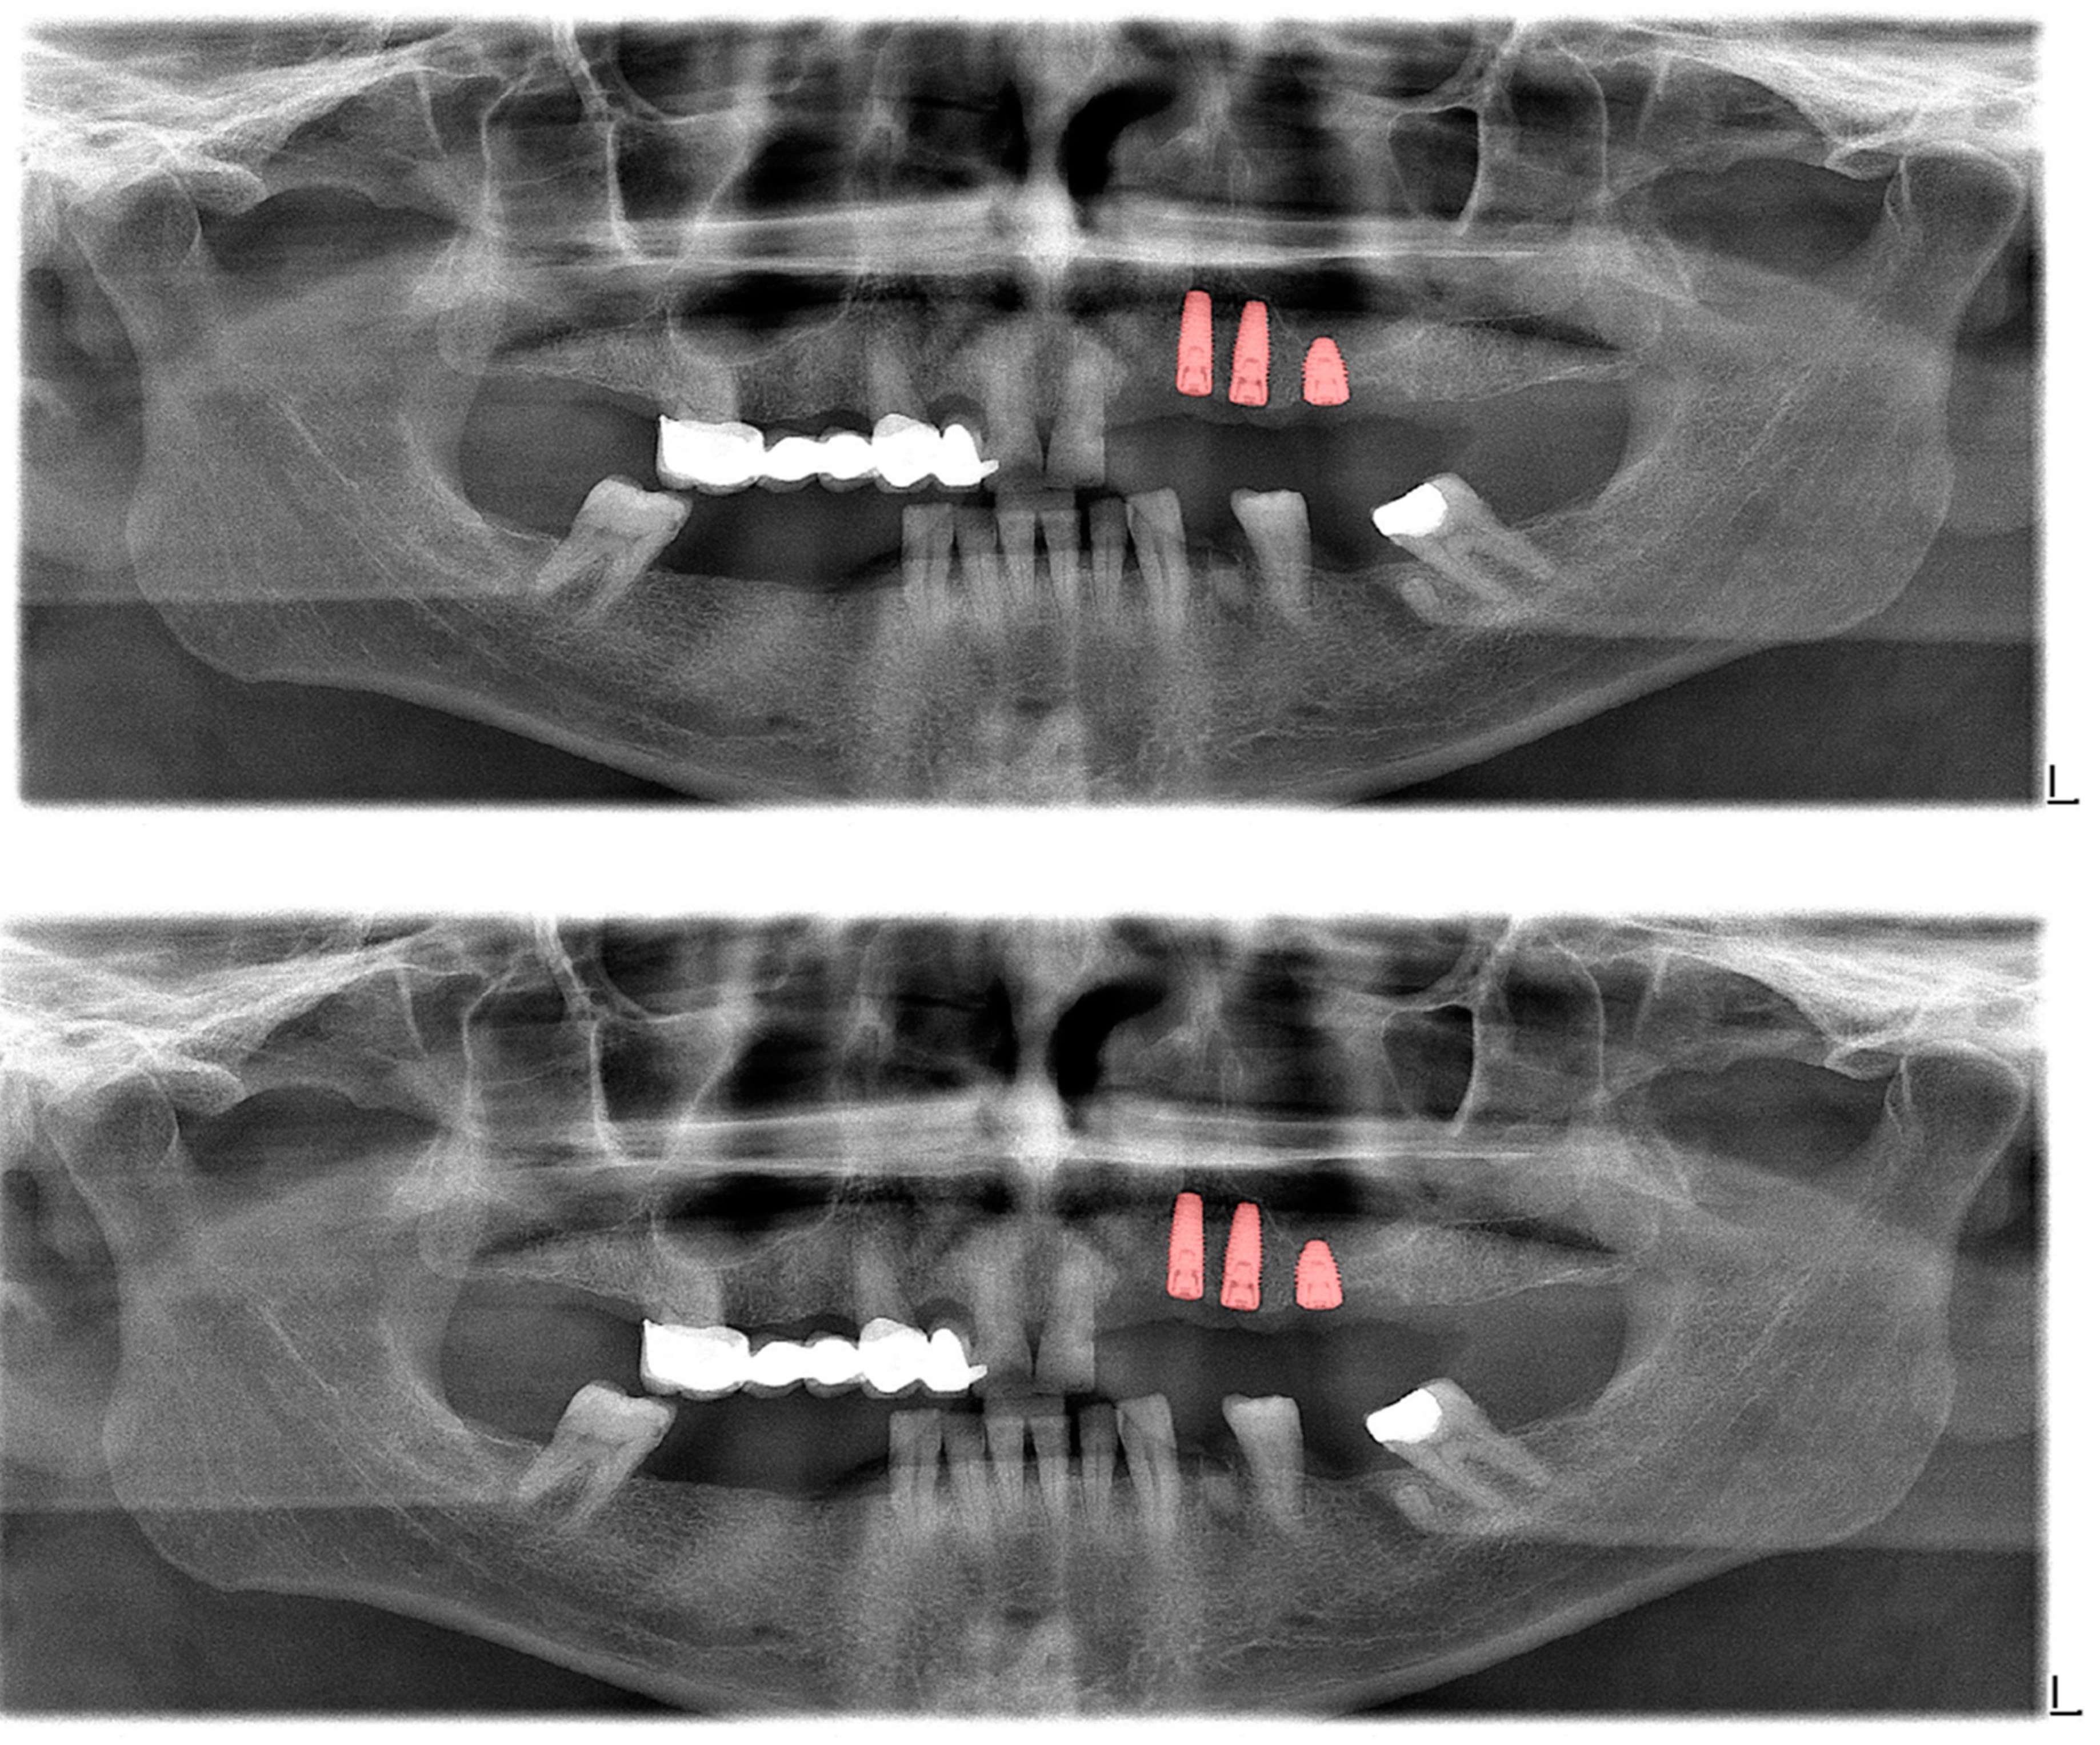

| Structure | DSC |

|---|---|

| Crown–bridge restorations (Figure 4) | 0.93 |

| Dental implants (Figure 5) | 0.94 |